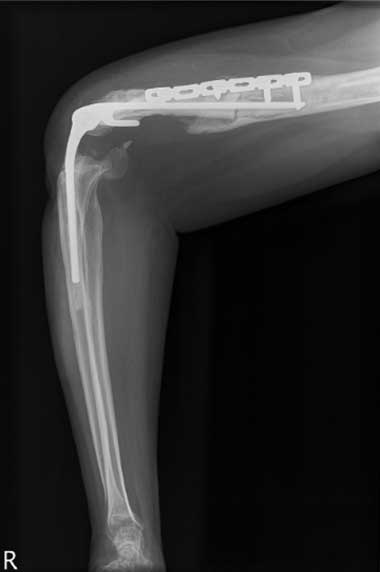

All 11 patients were taken to theatre within 24 hours of arrival at RPH and all underwent a washout and debridement. Depending on the injury, the procedures performed included open reduction and internal fixation; nerve, artery and tendon repair; and free flaps and split-skin grafting. Nine patients underwent multiple surgical procedures; 10 required open reduction and internal fixation with low contact dynamic compression plates for open fractures of the humerus, ulna and radius. The various plating procedures are illustrated in Box 2.

The most severe upper-arm injury involved Patient 7, with loss of the right distal humerus and olecranon, combined with an ulna nerve injury (Box 3). Initial treatment consisted of debridement and application of a bridging external fixator across the lost elbow joint (Box 4). This was complicated by iatrogenic radial nerve neuropraxia caused by the insertion of a Steinman pin. The external fixator was later replaced by a humeral allogeneic bone graft, an elbow prosthesis, and plate fixation of the humeral shaft (Box 5). The same patient also subsequently underwent a revision of the humeral plate procedure after a deep infection with Staphylococcus epidermidis was identified.